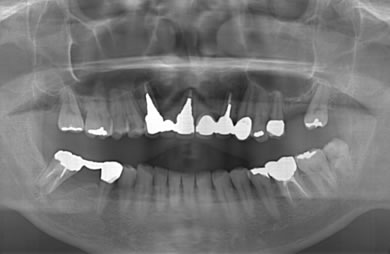

治療後

• 治療後